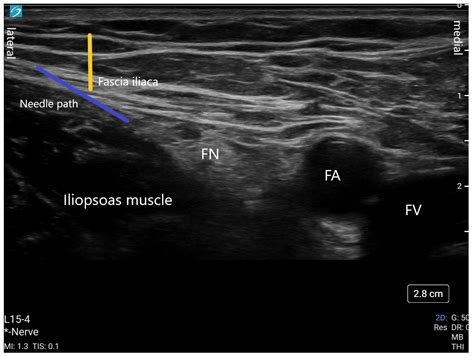

The ultrasound-guided technique has become the gold standard for performing a Femoral Nerve Block. It provides real-time visualization of the femoral nerve and surrounding structures, reducing the risk of complications and improving the success rate. The steps are as follows:

2. Place the ultrasound probe transversely over the inguinal crease to visualize the femoral nerve, artery, and vein.

3. Identify the femoral nerve, which appears as a hyperechoic structure lateral to the femoral artery.

4. Insert the needle in-plane with the ultrasound probe, aiming for the femoral nerve.

5. Aspirate to ensure the needle is not in a blood vessel, then inject the local anesthetic while visualizing the spread of the anesthetic around the nerve.

📌 Note: Ultrasound guidance requires specialized training and equipment but offers significant advantages in terms of accuracy and safety.